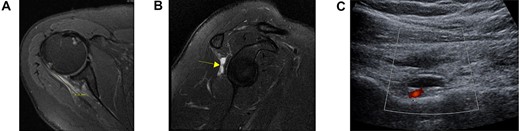

The index patient is a 52-year-old, right-hand dominant female with a history of right shoulder pain for 1 year. Initial physical examination was remarkable for full range of motion (ROM) and 5/5 rotator cuff strength. She was initially treated with physical therapy and a subacromial steroid injection, returning for a second steroid injection for pain recurrence 5 months later. After the second injection, she reported an acute exacerbation of shoulder pain originally treated as a steroid flare reaction. However, further imaging was obtained due to persistent shoulder pain and noted weakness in her arm. MRI and ultrasound sonography demonstrated a complete tear of IS MTJ with a fluid-filled gap, edema and mild muscle atrophy (Fig. 1A and B), in addition to a venous varix in the spinoglenoid (SG) notch (Fig. 1C). Given the unremitting pain and shoulder weakness despite conservative therapy, the patient elected for surgical repair 5 months after acute worsening of symptoms (Fig. 2A).

Axial (A) and sagittal (B) views of the preoperative MRI demonstrating a full-thickness tear at the level of the myotendinous junction with a fluid-filled gap (yellow arrow) and distal infraspinatus tendon stump attachment on the greater tuberosity. Ultrasound demonstrating a large, well-circumscribed hypoechoic lesion ultimately diagnosed as a venous varix adjacent to the suprascapular artery (C).